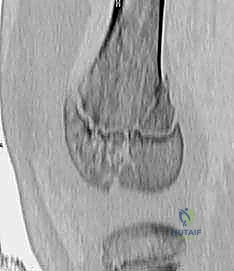

3. التصوير المقطعي المحوسب (CT Scan)

يطلبه الدكتور محمد هطيف في حالات الكسور المعقدة التي تمتد إلى داخل سطح المفصل (Intra-articular fractures). يساعد التصوير المقطعي ثلاثي الأبعاد في التخطيط الجراحي الدقيق لضمان إعادة السطح المفصلي إلى نعومته الطبيعية لمنع خشونة الركبة المبكرة.

النوع الثالث (Type III) والنوع الرابع (Type IV): الكسور داخل المفصل

هذه الكسور أكثر خطورة لأنها تخترق سطح المفصل وتدمر طبقات الخلايا الجذعية في صفيحة النمو.

* النوع الثالث (III): يبدأ الكسر من داخل المفصل، يمر عبر المشاشة (Epiphysis)، ثم يمتد أفقياً عبر صفيحة النمو.

* النوع الرابع (IV): كسر عمودي خطير. يمتد من السطح المفصلي للركبة، صعوداً عبر المشاشة، مخترقاً صفيحة النمو بالكامل، ومستمراً إلى داخل عظم الكردوس.

* التوقعات: تحمل هذه الإصابات داخل المفصل خطراً عالياً جداً لاضطرابات النمو، وتكوين جسور عظمية غير طبيعية (Physeal Bars)، وعدم تطابق الأسطح المفصلية (مما يؤدي لالتهاب المفاصل المبكر). تستدعي هذه الحالات تدخلاً جراحياً دقيقاً لإعادة العظم إلى وضعه التشريحي بدقة متناهية.